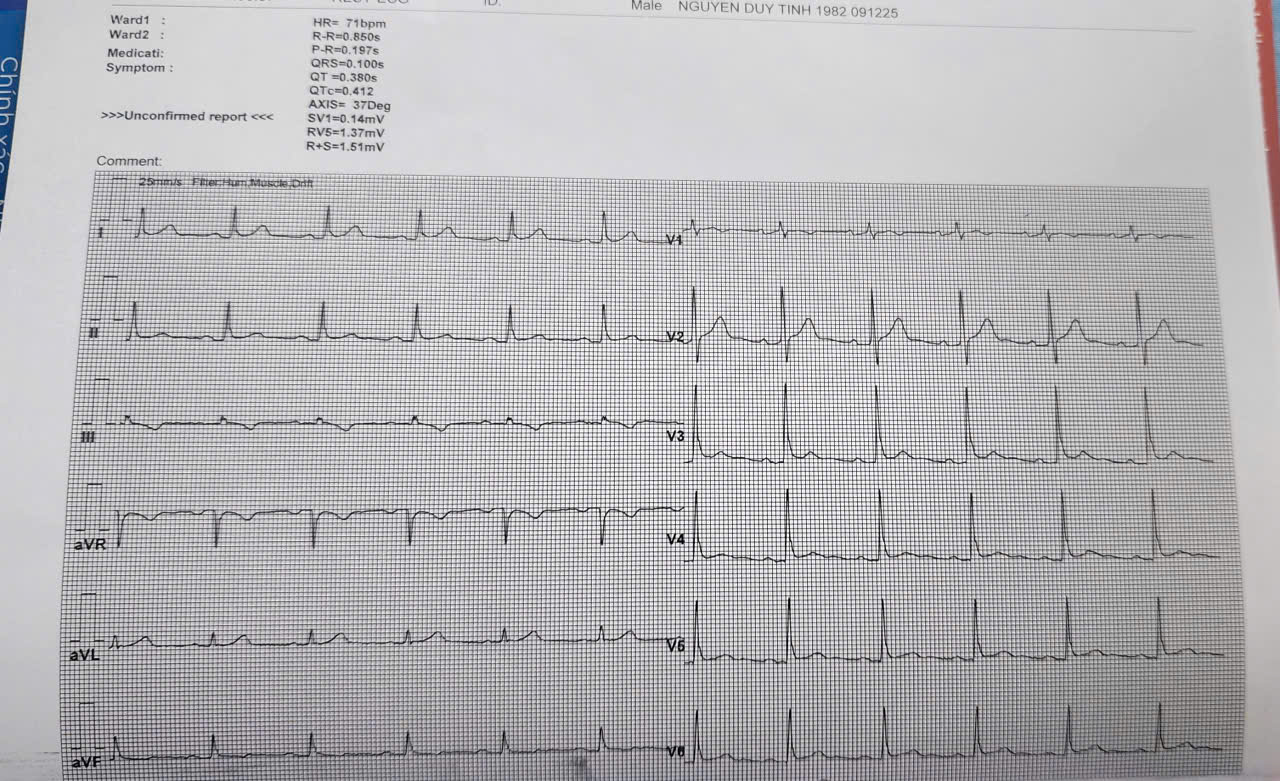

Gần đây, bằng việc ứng dụng trí tuệ nhân tạo, trên điện tim có thể dự báo được suy tim của bệnh nhân

ẢNH: DUY TÍNH